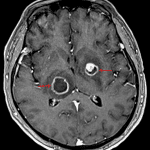

MRI

- Peripherally-enhancing lesions measuring up to 2.1 cm in the right thalamus and 1.5 cm in the left lentiform nucleus

- Internal T1 signal hypointensity and mild T2/FLAIR signal hyperintensity

- Corresponding peripheral restricted diffusion, more pronounced with the right thalamic lesion

- Surrounding T2/FLAIR signal hyperintensity and local mass effect with crowding of the third ventricle

CNS toxoplasmosis